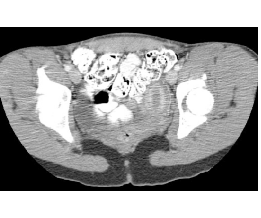

This patient was born with only one kidney on the left. Because the urinary and genital systems develop together, it is important to look for abnormalities of the uterus in patients with renal anomalies. In the pelvis in this patient, the uterus is an unusual shape, consistent with a unicornuate uterus, missing the right half. The IVC, left renal vein and external iliac veins, external iliac arteries and rectum are also shown on Image F, with unlabeled imag E.